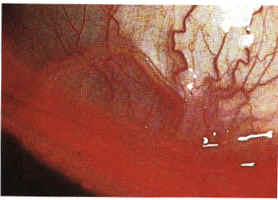

胸部丝虫病的发病过程主要分为两期:①早期:多为过敏反应和以渗出为主的炎症反应,微丝蚴和成虫的代谢产物、蜕皮液和蜕皮、成虫子宫内的分泌物、死亡的虫体及其分解产物等均可引起机体全身或局部过敏性反应,在肺部可表现为嗜酸粒细胞浸润,并出现哮喘、干咳、胸痛、血痰、气促等呼吸道症状;②慢性期:由于淋巴循环的特异性,胸内深部淋巴系统被嗜酸性肉芽肿或纤维化所堵塞,淋巴液回流障碍,堵塞以下的淋巴管扩张、压力增高甚至破裂,故出现乳糜胸水、乳糜痰等。